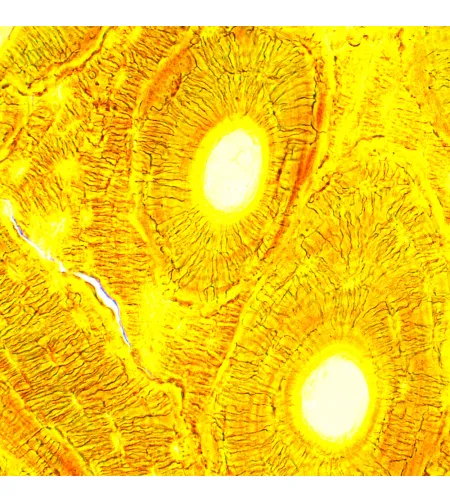

MAGUS Bio 250B biological microscope is an optical instrument used for studying thin transparent and translucent objects. Brightfield microscopy in transmitted light is the main microscopy technique. The microscope can be equipped with additional accessories for using darkfield, phase contrast, and polarization techniques. High-quality optics with additional options to expand its capabilities, easy-to-use mechanics, and smart design make this microscope an excellent choice for lab work, research, and teaching.

The microscope optics in the basic configuration provides magnification from 40 to 1000x. The use of additional eyepieces, if necessary, allows you to increase the upper limit of the magnification range.

| Application | laboratory/medical |